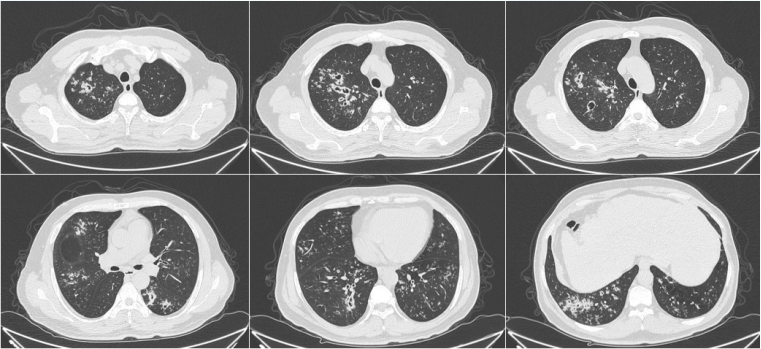

1. 影像学

IAPA的影像学表现为血管侵袭型和气道侵袭型。血管侵袭型包括晕征、楔形实变影、实变中的低密度坏死灶、空气新月征、空洞,多见于粒细胞缺乏患者。气道侵袭型包括小叶中心型结节影、沿气道分布的结节及斑片影、支气管壁增厚、“树芽征”等,多见于非粒细胞缺乏的免疫抑制患者。

图片

2  IAPA影像学表现

图源:中华结核和呼吸杂志2020年5月第43卷第5期.